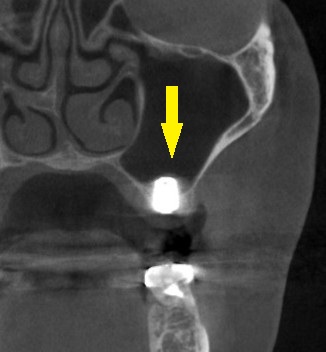

本日、同部に直径6mm、長さ8.5mmのワイドインプラントを埋入しました。

下の写真下段が手術後のCTです。